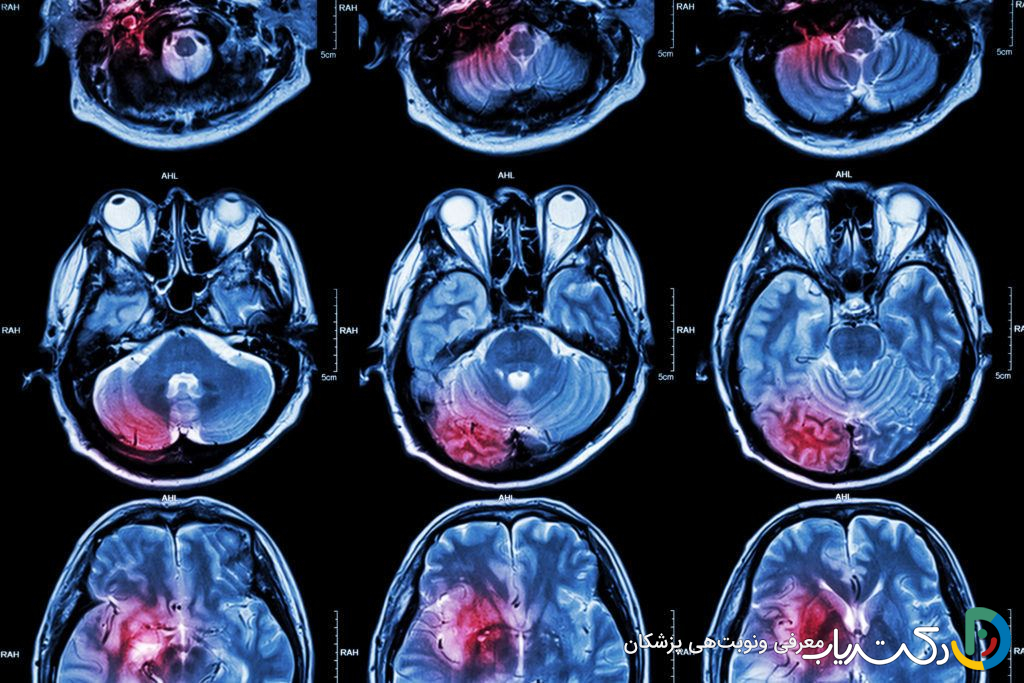

- MRI (تصویربرداری رزونانس مغناطیسی): این روش به عنوان استاندارد طلایی برای تشخیص تومورهای مغزی شناخته میشود. MRI با استفاده از میدانهای مغناطیسی قوی و امواج رادیویی، تصاویر بسیار دقیقی از ساختارهای نرم مغز ارائه میدهد. اغلب از یک ماده حاجب (مانند گادولینیوم) برای تزریق وریدی استفاده میشود که در نواحی با عروق خونی غیرطبیعی (مانند تومورها) جمع شده و باعث درخشان شدن آنها در تصاویر میشود. انواع پیشرفته MRI مانند fMRI (نقشهبرداری از مراکز عملکردی مغز)، DTI (نمایش مسیرهای عصبی) و MRS (تحلیل ترکیب شیمیایی تومور) به جراحان در برنامهریزی برای جراحی ایمن کمک میکنند.